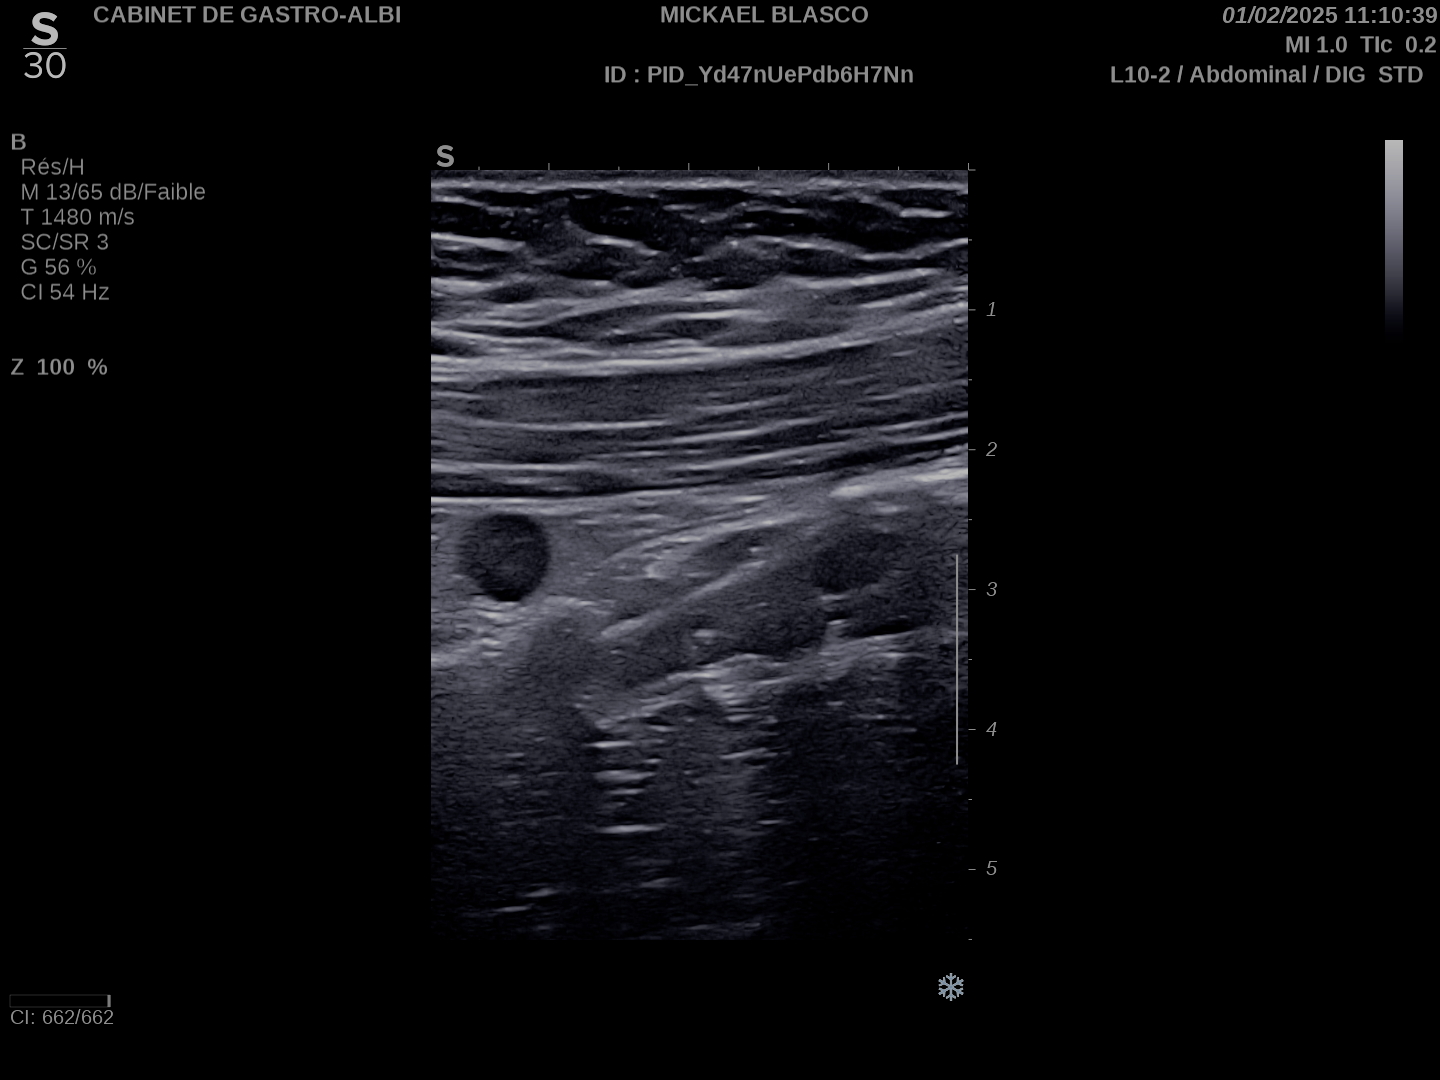

Epaississement entre 4.5 et 7 mm selon les segment, la structure en couche disparait totalement par endroit, à d’autre elle est partiellement conservée. Activité doppler intense de la paroi

Le Score de Milan (MUC) est à (1,4 x7+2) = 11,8